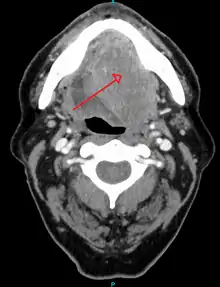

- better assess the size of the lesion (CT scan, MRI or PET scan with 18F-fluorodeoxyglucose (FDG)),[36]: 143

- spread to the lymph nodes (CT scan) or